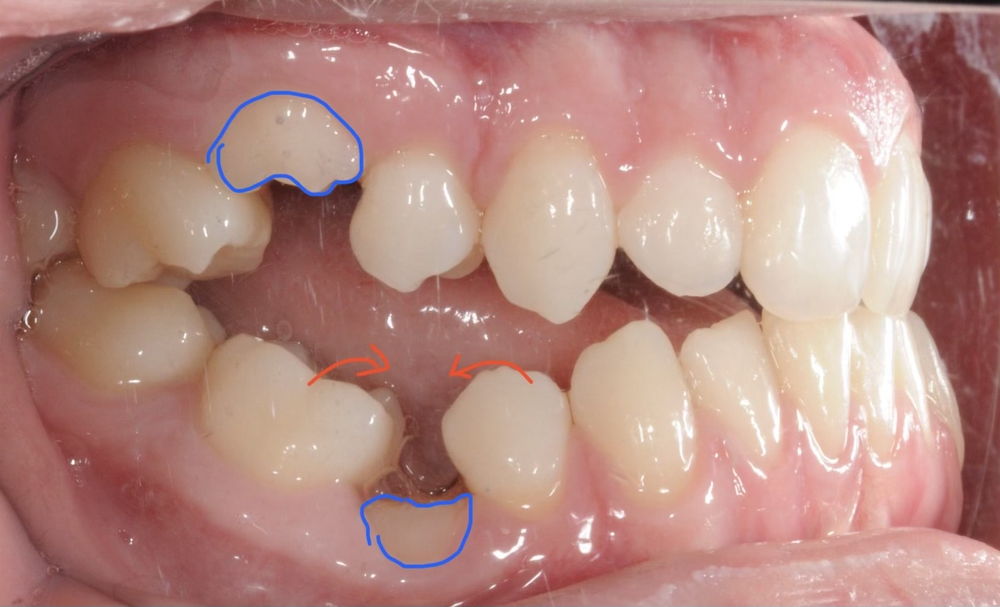

Smile Makeover Cosmetic Bonding on retained deciduous ( Baby tooth Orthodontics Retained Baby Teeth Baby teeth with no underlying permanent replacements may be retained indefinitely. While it’s true that baby teeth are temporary, retained baby teeth can lead to various complications, including orthodontic issues and improper eruption of permanent teeth. When the tooth remains in place, orthodontics may be used to prevent bite problems. Sometimes, a child’s baby teeth get loose but then tighten. Orthodontics Retained Baby Teeth.

From www.shakespeareortho.co.nz

Orthodontic Changes Before & After with Braces and Invisalign Orthodontics Retained Baby Teeth Sometimes, a child’s baby teeth get loose but then tighten up again, preventing the permanent teeth from erupting. Additionally, a crown may be placed on the tooth to give it the look and size of an adult tooth. Extra teeth can block the normal eruption of the regular permanent ones. Adult baby teeth often occur due to a lack of. Orthodontics Retained Baby Teeth.